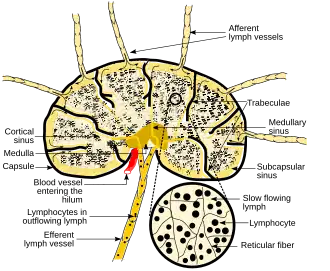

Diagram showing major parts of a lymph node | |

In the lymphatic system, a lymph node is a secondary lymphoid organ. A lymph node is enclosed in a fibrous capsule and is made up of an outer cortex and an inner medulla.

Each lymph node is surrounded by a fibrous capsule (made of collagenous connective tissue),[3] which extends inside a lymph node to form trabeculae.[4] The substance of a lymph node is divided into the outer cortex and the inner medulla.[4] These are rich with cells.[5] The hilum is an indent on the concave surface of the lymph node where lymphatic vessels leave and blood vessels enter and leave.[5]

Lymph enters the convex side of a lymph node through multiple afferent lymphatic vessels, and from there, it flows into a series of sinuses. Upon entering the lymph node, lymph first passes into a space beneath the capsule known as the subcapsular sinus, then moves into the cortical sinuses. After traversing the cortex, lymph collects in the medullary sinuses. Finally, all of these sinuses drain into the efferent lymphatic vessels, which carry the lymph away from the node, exiting at the hilum on the concave side.

Subdivisions

A lymph node is divided into compartments called nodules (or lobules), each consisting of a region of cortex with combined follicle B cells, a paracortex of T cells, and a part of the nodule in the medulla.[17] The substance of a lymph node is divided into the outer cortex and the inner medulla.[4] The cortex of a lymph node is the outer portion of the node, underneath the capsule and the subcapsular sinus.[17] It has an outer part and a deeper part known as the paracortex.[17] The outer cortex consists of groups of mainly inactivated B cells called follicles.[5] When activated, these may develop into what is called a germinal center.[5] The deeper paracortex mainly consists of the T cells.[5] Here the T-cells mainly interact with dendritic cells, and the reticular network is dense.[18]

The medulla contains large blood vessels, sinuses and medullary cords that contain antibody-secreting plasma cells. There are fewer cells in the medulla.[5]

The medullary cords are cords of lymphatic tissue, and include plasma cells, macrophages, and B cells.

Lymph enters the convex side of a lymph node through multiple afferent lymphatic vessels, which form a network of lymphatic vessels (Latin: plexus) and flows into a space (Latin: sinus) underneath the capsule called the subcapsular sinus.[5][4] From here, lymph flows into sinuses within the cortex.[4] After passing through the cortex, lymph then collects in medullary sinuses.[4] All of these sinuses drain into the efferent lymphatic vessels to exit the node at the hilum on the concave side.[4]

These are channels within the node lined by endothelial cells along with fibroblastic reticular cells, allowing for the smooth flow of lymph. The endothelium of the subcapsular sinus is continuous with that of the afferent lymph vessel and also with that of the similar sinuses flanking the trabeculae and within the cortex. These vessels are smaller and do not allow the passage of macrophages so that they remain contained to function within a lymph node. In the course of the lymph, lymphocytes may be activated as part of the adaptive immune response.

There is usually only one efferent vessel though sometimes there may be two, in contrast to the multiple afferent channels that bring lymph into the node.[22] Medullary sinuses contain histiocytes (immobile macrophages) and reticular cells, the former of which, along with T and B cells, become activated in the presence of antigens through lymphatic flow. The fewer efferent vessels allow this flow to be slowed, providing time to activate and distribute a larger number of immune cells in the event of an infection.

Capsule

Thin reticular fibers (reticulin) of reticular connective tissue form a supporting meshwork inside the node.[5] These reticular cells also form a conduit network within the lymph node that functions as a molecular sieve, to prevent pathogens that enter the lymph node through afferent vessels re-enter the blood stream.[24] The lymph node capsule is composed of dense irregular connective tissue with some plain collagenous fibers, and a number of membranous processes or trabeculae extend from its internal surface. The trabeculae pass inward, radiating toward the center of the node, for about one-third or one-fourth of the space between the circumference and the center of the node. In some animals they are sufficiently well-marked to divide the peripheral or cortical portion of the node into a number of compartments (nodules), but in humans this arrangement is not obvious. The larger trabeculae springing from the capsule break up into finer bands, and these interlace to form a mesh-work in the central or medullary portion of the node. These trabecular spaces formed by the interlacing trabeculae contain the proper lymph node substance or lymphoid tissue. The node pulp does not, however, completely fill the spaces, but leaves between its outer margin and the enclosing trabeculae a channel or space of uniform width throughout. This is termed the subcapsular sinus (lymph path or lymph sinus). Running across it are a number of finer trabeculae of reticular fibers, mostly covered by ramifying cells.